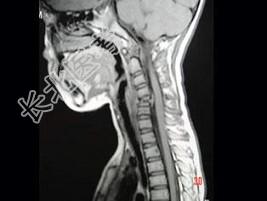

- 单项选择题男,37岁, 颈部疼痛,活动时加重, 休息可减轻,夜间有盗汗, 结合图像,最可能的诊断是 ( )

D、颈椎结核